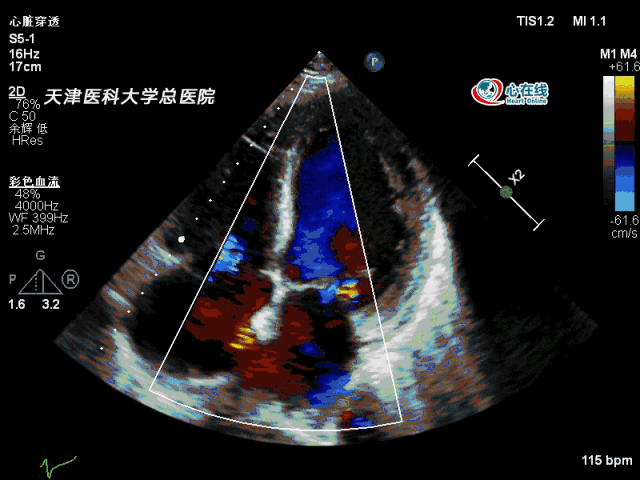

入院后行经胸心脏超声和经食道超声检查提示:la 42mm,lv 48mm,lvef

心房纤颤的超声表现